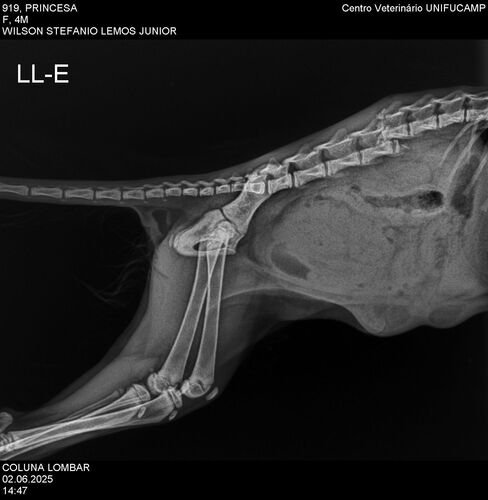

Durante as primeiras semanas com ela, investigamos as origens dela até conseguirmos o contato do homem que a encontrou. Conversamos com ele e soubemos que, ao resgatá-la, ele a levou para fazer exames e tentou viabilizar uma cirurgia na coluna. No entanto, o hospital recusou realizar o procedimento e sugeriu a eutanásia. Ele não queria aceitar essa opção, então, chegaram a um acordo: colocariam a gatinha para adoção e, caso ninguém a adotasse, fariam a eutanásia. Foi assim que ela entrou em nossas vidas.

Preocupadas com sua condição e buscando segundas opiniões, levamos a gatinha a uma veterinária especializada em fisioterapia. Após analisar os exames, ela nos orientou a realizar a cirurgia, que pode melhorar muito sua qualidade de vida e até possibilitar que volte a andar. Por indicação dessa profissional, encontramos um veterinário que realiza o procedimento por R$ 2.500,00.